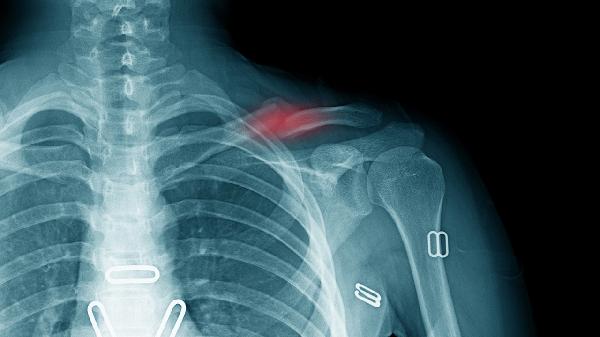

左肩锁骨下面阵痛怎么回事

左肩锁骨下方阵痛可能与肌肉劳损、颈椎病、肩周炎、胸廓出口综合征、肋软骨炎等因素有关,可通过休息理疗、药物干预、康复训练等方式缓解。